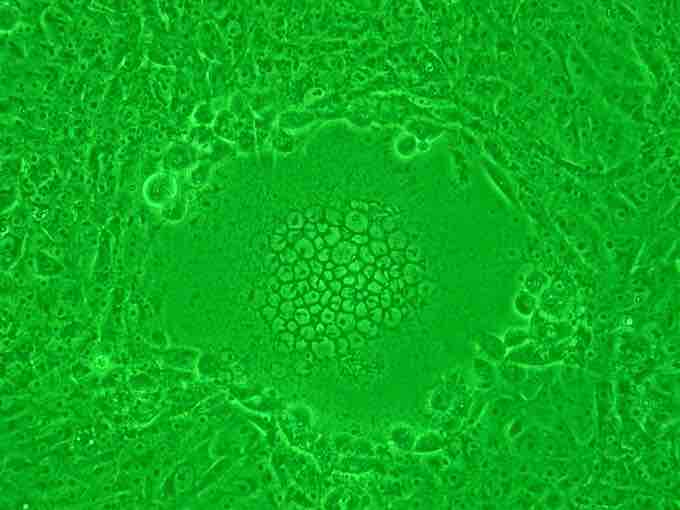

Syncytium

The mass or "ball" of cells in the middle of the image are a syncytium of cells that formed due to infection by the HIV virus.

Syncytia are aggregates of cells that can form when cells are infected with certain types of viruses, notably HIV and paramyxoviruses such as RSV. During infection, viral fusion proteins used by the virus to enter the cell are transported to the cell surface where they can cause the host cell membrane to fuse with neighboring cells. This presumably works to the virus's advantage, as aggregates of target cells provide more hosts for the virus to infect and multiply. F proteins also mediate viral fusion, allowing entry of the virus into the cell cytoplasm and also allowing the formation of syncytia. Antibodies directed at the F protein are neutralizing. M2 is the second matrix protein required for viral transcription; it encodes M2-1 (elongation factor) and M2-2 (transcription regulation), while L encodes the RNA polymerase. The phosphoprotein P is a cofactor for L. The genome is transcribed sequentially from NS1 to L with reduction in expression levels along its length.